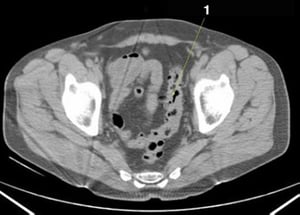

CT-Scan von Abdomen und Becken mit normaler Anatomie ohne Kontrastmittel (Folie 25)

1 = Colon sigmoideum.

© Springer Science+Business Media